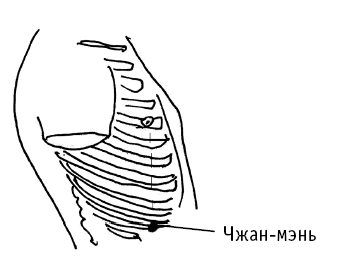

Чжан-мэнь («светлые ворота») расположена у конца 11-го ребра (рис. 5, б). Точку находят и воздействуют на нее в таком положении: пациент лежит на боку, нижняя нога выпрямлена, верхняя нога согнута, рука поднята.

Надавливание используют при чрезмерном брожении в кишечнике, жидком стуле, снижении аппетита, вялости, рвоте, болях в подреберье, отрыжке.

Воздействие на точку благотворно: при климактерическом неврозе, утомляемости от физической нагрузки, бессоннице; при болях в пояснице, частом мочеиспускании, у мужчин – при белых мутных выделениях из полового члена; при кашле, одышке, сухости в горле.

Чжан-мэнь («светлые ворота») расположена у конца 11-го ребра (рис. 5, б). Точку находят и воздействуют на нее в таком положении: пациент лежит на боку, нижняя нога выпрямлена, верхняя нога согнута, рука поднята.

Надавливание используют при чрезмерном брожении в кишечнике, жидком стуле, снижении аппетита, вялости, рвоте, болях в подреберье, отрыжке.

Воздействие на точку благотворно: при климактерическом неврозе, утомляемости от физической нагрузки, бессоннице; при болях в пояснице, частом мочеиспускании, у мужчин – при белых мутных выделениях из полового члена; при кашле, одышке, сухости в горле.